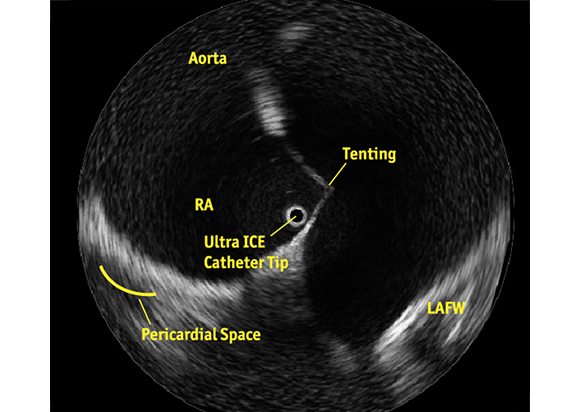

ULTRA ICE PLUS catheter positioned in the right atrium, adjacent to the fossa ovalis, visualizing the structures critical to successful transseptal puncture: the septum, aorta, needle position, tenting, and the LAFW.

See What You Want to Avoid

Notice the patient’s reduced Left Atrium, the tenting of the septum and its relationship to the LAFW. The corresponding fluoroscopic image may suggest that puncture has already occurred. However, the ULTRA ICE PLUS image shows that this is not the case and guides the physician to redirect the needle in a puncture angle away from the LAFW.